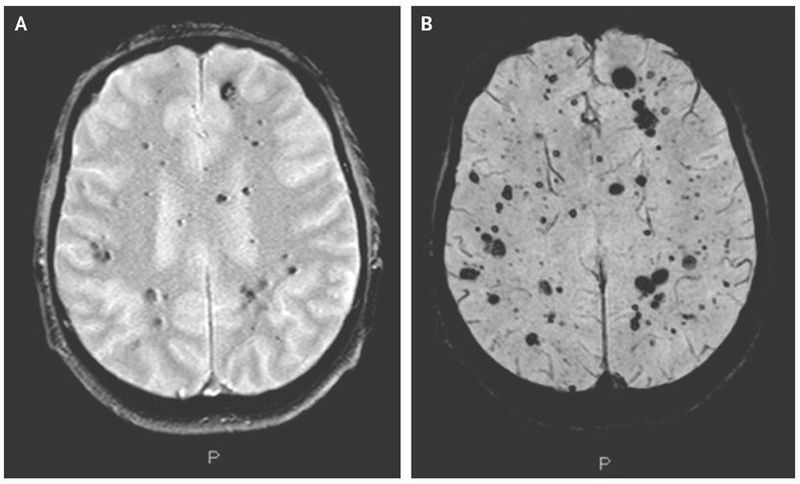

A 59-year-old man presented to an outpatient clinic with a 1-year history of progressively worsening headaches. Neurologic examination was normal; skin examination revealed multiple hyperkeratotic papules and bluish, nodular skin lesions. Magnetic resonance imaging of the brain revealed numerous lesions consistent with cerebral cavernous malformations involving the cerebral hemispheres, cerebellum, and brain stem (Panel A shows a T2-weighted, fast field echo image, and Panel B a blood oxygenation level–dependent image; P denotes posterior). Cavernous malformations occur primarily in the brain but may also be found in the skin, spinal cord, and retina. A proportion of patients with cerebral cavernous malformations are asymptomatic, whereas others present with neurologic symptoms, such as seizures, headaches, and even fatal cerebral hemorrhage. Cerebral cavernous malformations can be sporadic or familial. The patient’s mother and maternal grandfather had cutaneous lesions similar to those in our patient but had not undergone brain imaging. Genetic analysis in our patient revealed a mutation in KRIT1 (also called CCM1) that was compatible with the diagnosis of the familial cerebral cavernous malformation syndrome. Owing to the vast number of cerebral cavernous malformations, neurosurgical treatment was not an option. This patient continues to have intermittent headaches, which are partially alleviated by beta-blockers. Mild cognitive decline with memory deficits has also developed.